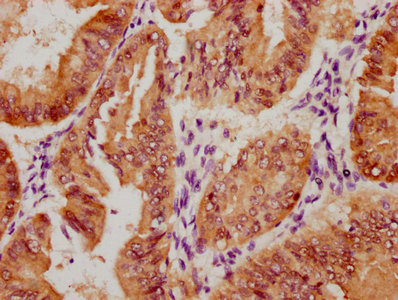

圖片:

應用范圍:ELISA, IHC

Application Recommended Dilution IHC 1:20-1:200 -